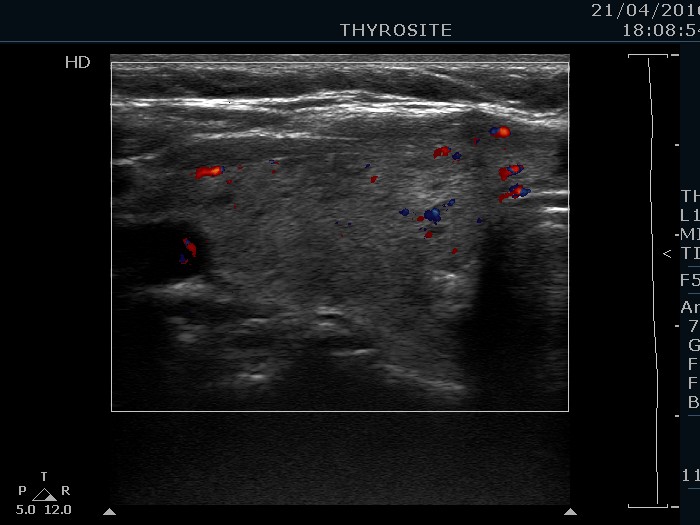

Left lobe, longitudinal scan, color Doppler mode. The vascularization is average.